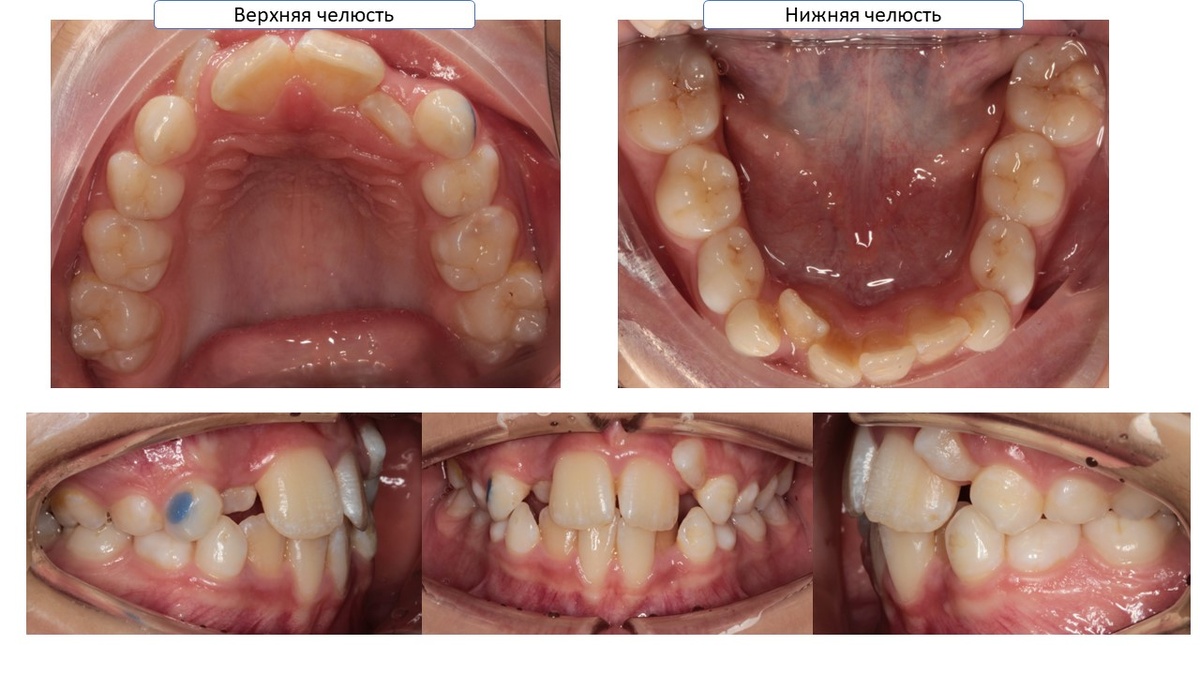

Наша Таня выглядит теперь так!

-9

И мы должны вернуть пространство, которое заняли у других постоянных зубов.

-10

Да! Как бы ужасно это не выглядело! Мы удаляем Первые постоянные премоляры!

Тане 12 лет